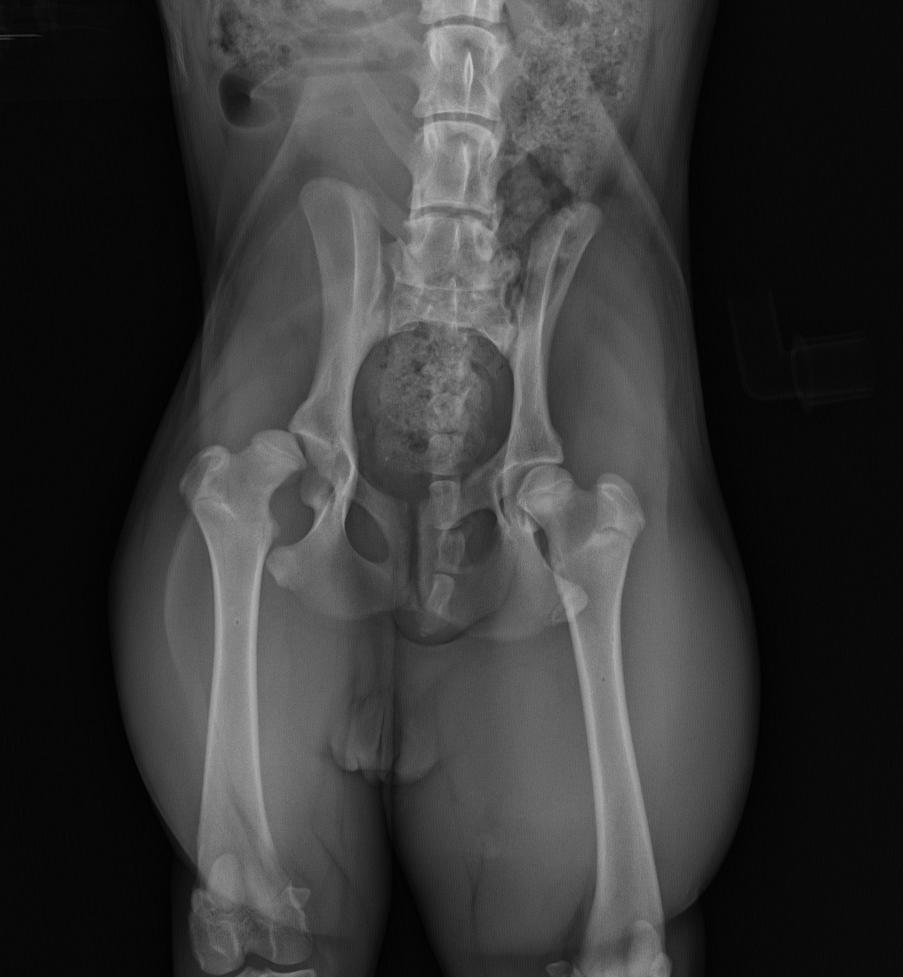

Hip and elbow dysplasia are two relatively common conditions that can affect the skeleton of the dog.

More commonly seen in large and giant breed dogs, dysplasia can occur in dogs of any size or breed (or mixes of breeds).

The word dysplasia means ‘abnormal growth or development’.

What is hip dysplasia?

Hip dysplasia occurs when there is abnormal development of the hip joint - a ball and socket type joint. The result is that the ball and socket end up not fitting together properly, leading to altered joint function.

Instead of sliding smoothly against each other during everyday movement, the two joint surfaces end up rubbing and grinding against each other due to the abnormal shape and position of the ball relative to the socket.

What is elbow dysplasia?

In the front leg, elbow dysplasia refers to a number of different conditions that affect the three bones that form the elbow joint. These changes may occur alone or in combination, but the result is the same - a joint that does not function properly.

Both hip and elbow dysplasia can be quite painful and. over time, can lead to increased wear of the joint surfaces, the development of osteoarthritis, and a reduced range of movement.

At what age is dysplasia usually diagnosed?

Because dysplasia relates to abnormal growth and development, symptoms are most commonly seen in young, growing animals - usually dogs under 12 months of age - with varying degrees of lameness, pain, or reluctance to exercise.

However, some animals with abnormal joint development may not have any obvious symptoms or display signs of pain or reduced movement until later in life when arthritis develops in the joint.

How is hip or elbow dysplasia diagnosed?

In most cases, diagnosis is confirmed by an x-ray examination of the affected joint or joints. Specific positions are used to evaluate both the hips and elbows by x-ray, and sedation of the animal may be required.

Your veterinarian will be looking at the shape and fit of the joint, as well as for signs of arthritis developing within the joint.

Dysplasia is thought to have several contributing factorswith the biggest risk factor being genetics.

This genetic ‘potential’ for dysplasia can be further exacerbated by poor/unbalanced nutrition, over-feeding and obesity, rapid weight gain and growth, and early joint stress caused by certain types of exercise.

Instead, reputable breeders actively partake in screening programs that use x-ray pictures to look at hip and elbow anatomy of potential breeding stock before they are bred from.

Screening programs involve specialist Veterinary Radiologists examining the hip and elbow x-rays of potential breeding stock and grading them using one of a number of internationally accepted protocols.

In Australia, the most widely used scoring protocol is the British Veterinary Association (BVA) scheme. This system gives a numerical score to nine different aspects of each hip joint.

The scores are then totalled for each hip, with a ‘0’ score representing the best result and 53 the worst possible result for each hip. The scores for the two hips are then added to give a total score (from 0 to 106), and this is what is compared to the breed average.

For a score to be recorded on the Dogs Australia ‘ORCHID’ database (Officially Registered Canine Health Information Database), the x-rays must be scored by one of the Veterinary Radiologist panellists listed on the ORCHID website. Scoring for official results can only be done on animals over 12 months of age.

Another protocol for assessing hip conformation is the PENN Hip evaluation developed by veterinarians at the University of Pennsylvania.

The PENN Hip screening technique uses different body positions compared to the BVA testing. This protocol looks at ‘passive hip laxity’ - the degree of looseness in the hip joint when the muscles are completely relaxed. This scoring can be done from 16 weeks of age.

The result is shown as a ‘distraction index’, and breeders aim to select animals with ‘tighter hip joints’ than the breed average.